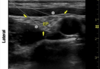

Name this block, and what are the white arrow indicating?

ISB intermediate/superficial cervical plexus

36

What does this image show?

initial supraclavicular probe placement for ISB where BP runs next to (lateral) subclavian artery

37

How do you achieve this view?

Start with US probe in supraclavicular position, then sweep probe cephalicly until you get this view